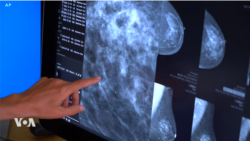

តើបញ្ញាសប្បនិម្មិត AI អាចកំណត់រកជំងឺមហារីកសុដន់បានប្រសើរជាងវេជ្ជបណ្ឌិតឬទេ?

ការសិក្សាមួយកាលពីពេលថ្មីៗនេះបង្ហាញថា វេជ្ជបណ្ឌិតអាចកំណត់ឃើញជំងឺមហារីកសុដន់ច្រើនដងជាងមុន នៅពេលពួកគេប្រើប្រាស់បញ្ញាសប្បនិម្មិត AIដើម្បីជួយពិនិត្យលទ្ធផលស្កេនសុដន់។ AI ជួយបង្កើនអត្រាកំណត់ឃើញជំងឺមហារីកសុដន់បានច្រើនជាងមុន ១៧ភាគរយ។ អ្នកស្រី Dora Mekouar នៃវីអូអេជូនសេចក្តីរាយការណ៍។ អ្នកនាងស្រេង លក្ខិណាសូមជូនសេចក្តីប្រែសម្រួលដូចតទៅ៖